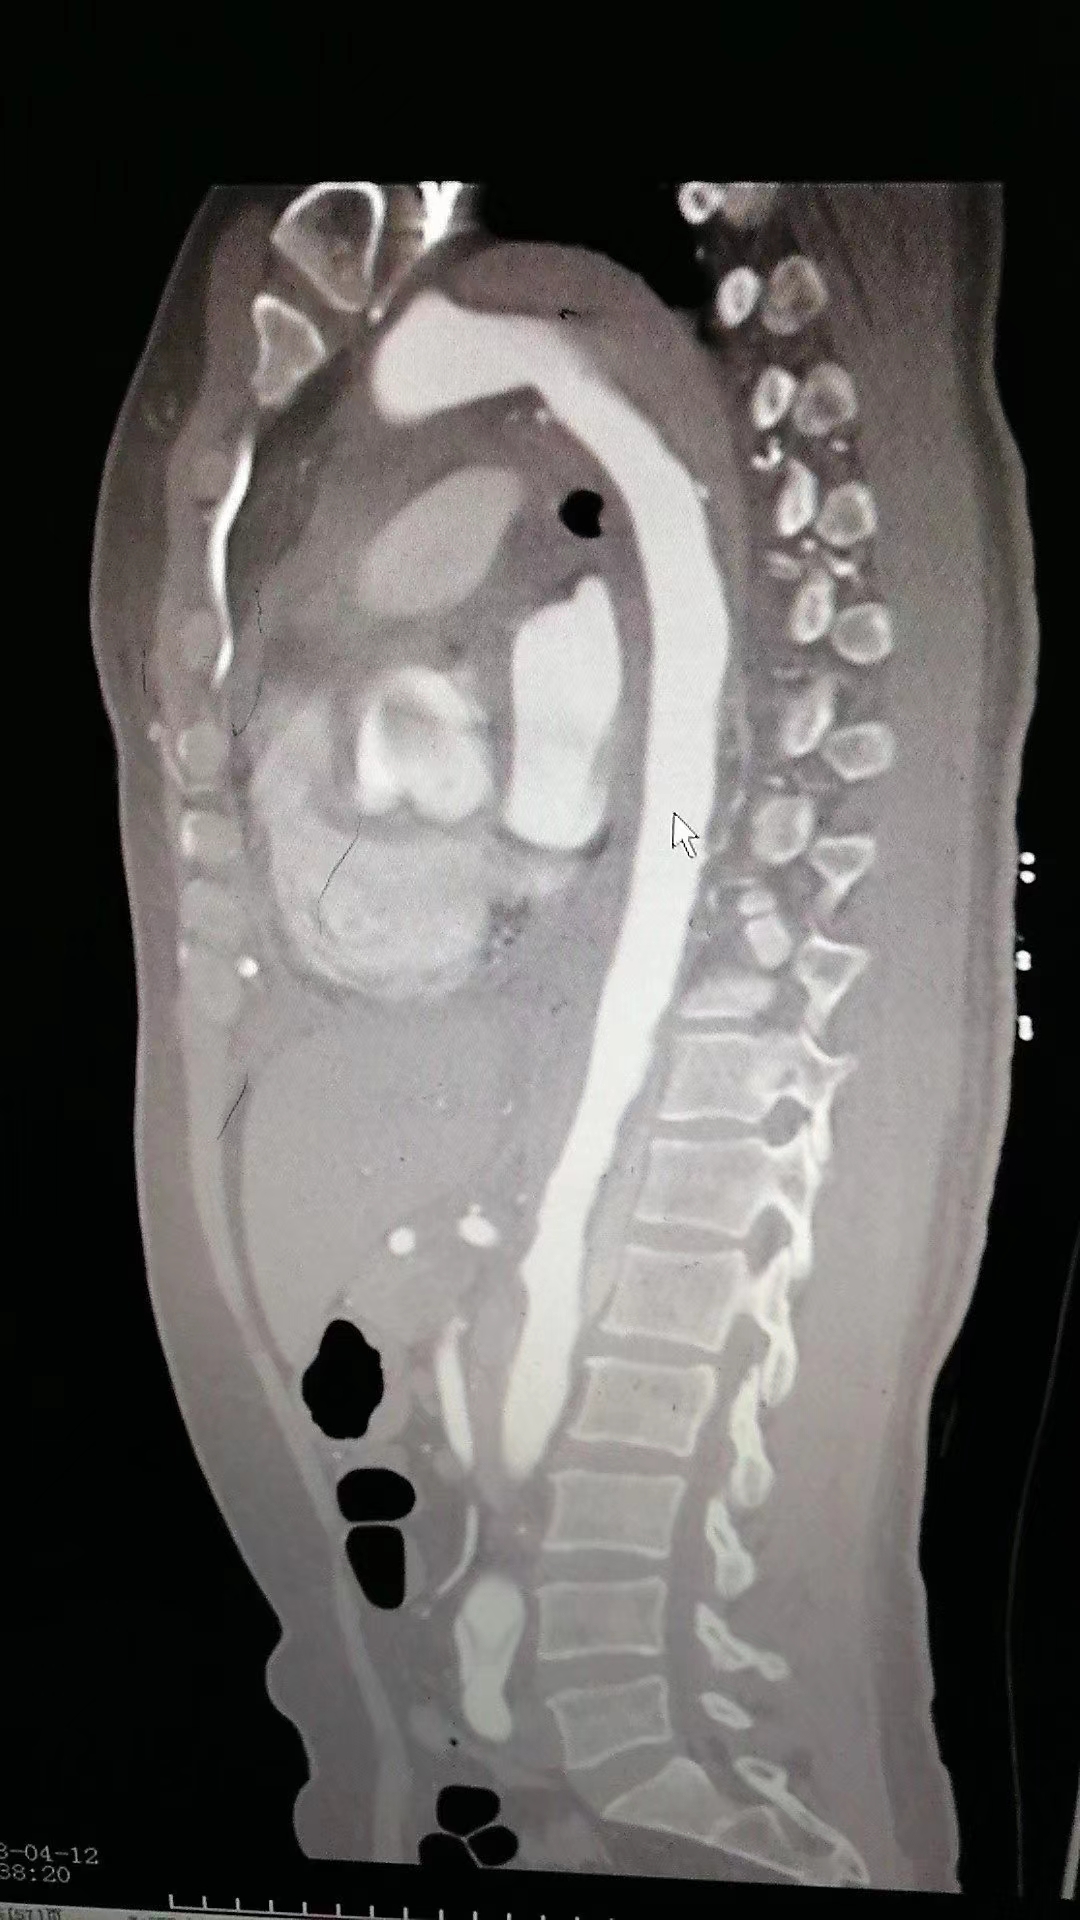

反复询问患者后一个细节引起了我的注意,患者描述她最开始只是颈部疼痛,不知道怎么回事疼痛一下就窜到腰部去了,这让我联想到了主动脉夹层。于是我立即与患者及家属沟通后完善了主动脉CTA,主动脉CTA提示主动脉夹层I型。后来这个病人转院做了主动脉置换手术,手术很顺利,术后患者也恢复得很好。

影像学检查目的是要对全主动脉进行综合评价,包括受累的范围、形态、不同部位主动脉的直径、主动脉瓣及各分支受累情况、与周围组织的关系,以及其他相关表现如心包积液、胸腔积液及脏器缺血情况等。